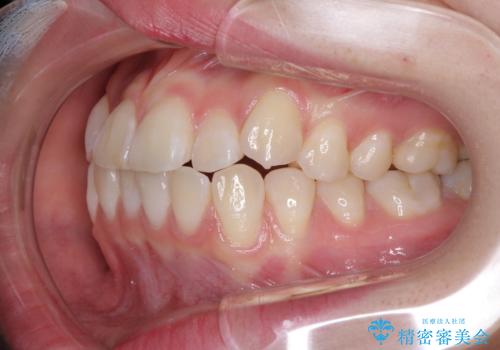

- 海外留学の予定があるが、学生のうちに歯列を整えたいとのことで来院された患者様です。

前歯にデコボコがあり、口元がやや突出した印象があったため、IPR(歯と歯の間を削る)と親知らずを抜歯した上での歯列全体の後方移動をメインに、インビザラインを用いて矯正治療を行うこととしました。

年に一度、夏休みの時期にしか帰国できないため、帰国のタイミングに合わせてマウスピース交換スケジュール治療計画としたため、3年半という期間を要しました。

留学先でもしっかりとマウスピースの装着を実践してくださったので、ご本人の満足のいく仕上がりとなりました。